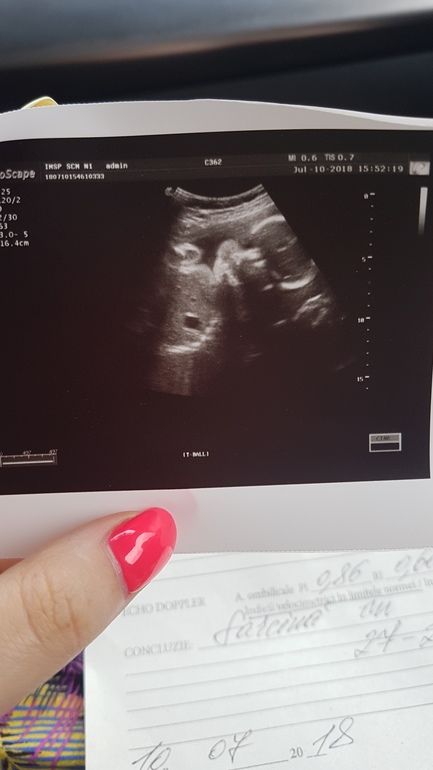

Вы видите ребенка на этом фото?!!))))))

Вопросы про УЗИ, обследования и анализы: что, где, как, когда?Были мы сегодня на узи я все пыталась даже во время узи увидеть малютку но у меня не получалось)))муж говорит видел а я чет никак)))так мы и крупненькие довольно 1,050 кг это в начале то 27 недели)))боюсь на фруктах не дойти бы нам до 4-х)))

Прилагаю фото))девочки более опытные в загадках узи покажите мне тетере гду тут дитя))))

Голова на фото,у меня такое же,фиг понять что это.Так как малышь большой и не помещается на экран весь.

Лицо и ручки))) кружки по краям плеч это ручки))

Бусинки дугой слева - Это позвоночник, над ними рука, справа голова, она повернута к нам, вижу пухлые щечки, глаза, нос.

Да, конечно. Бусинки слева внизу - это точно позвоночник, над ним ручка согнутая, все что справа - это головка. Посмотрите внимательно и Вы увидете, Ваш малыш смотрит прямо на Вас.